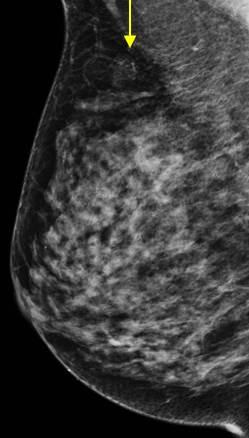

Ung thư vú

Ung thư vú - Ảnh 2

» Thông tin: Nữ giới – 41 tuổi.

» Lâm sàng: Khối tuyến vú.